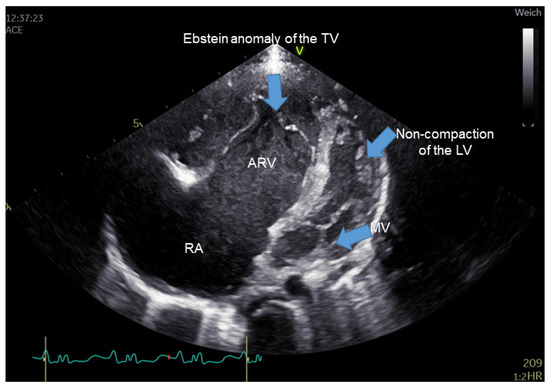

Clinical characteristics of EA patients are displayed in Supplementary Table S1. The mean age of EA patients was 25.8 ± 12.4 years; the mean weight was 63.7 ± 14 kg, and the mean height was 165 ± 8.12 cm. Following the Carpentier criteria, the severity of EA could be classified as mild in 5/16 patients (31.25%), moderate in 9/16 patients (56.25%), and severe in 2 patients (12.50%). Figure 1 shows a representative 2-dimensional echocardiographic result for EA patients. One patient (1/16, 6.25%) underwent reconstructive surgery for the tricuspid valve. Four patients originated from one family with different degrees of EA (25.0%).

Figure 1. Transthoracic echocardiographic image showing the four-chamber view. The characteristic malformation of severe Ebstein’s anomaly of tricuspid valve in the right heart is clearly seen with an apical displacement of the septal leaflet of the tricuspid valve, leading to marked enlargement of the right atrium and atrialized right ventricle (ARV). The left ventricle shows prominent apical trabeculation suggestive of non-compaction of the left ventricle. ARV, atrialized portion of the right ventricle (ARV); TV, Tricuspid valve; MV, mitral valve; LV, left ventricle; RA: right atrium.